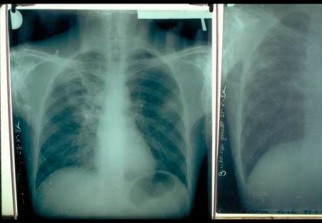

Le nombre des personnes atteintes de la maladie de la tuberculose dans la wilaya d'Oran, a connu une baisse de 40 pour cent depuis 2009, a-t-on appris jeudi du responsable du service prévention à la direction de la santé et de la population de la wilaya. Ce nombre est passé de 1.573 en 2012, à 1.423 cas en 2013, a ajouté Dr Deharib Larbi.

Le nombre de personnes atteintes de cette maladie a également diminué en milieu scolaire de 50 pour cent. Le bureau de santé scolaire à la direction de la santé a enregistré seulement trois cas en 2013 contre six en 2012, souligne la même source."Cette baisse est due à l'application stricte de la stratégie de lutte contre la tuberculose, à la disponibilité régulière du médicament, à la prise en charge et le suivi continu du malade et au dépistage en milieu familial évitant la propagation", a t-on ajouté.